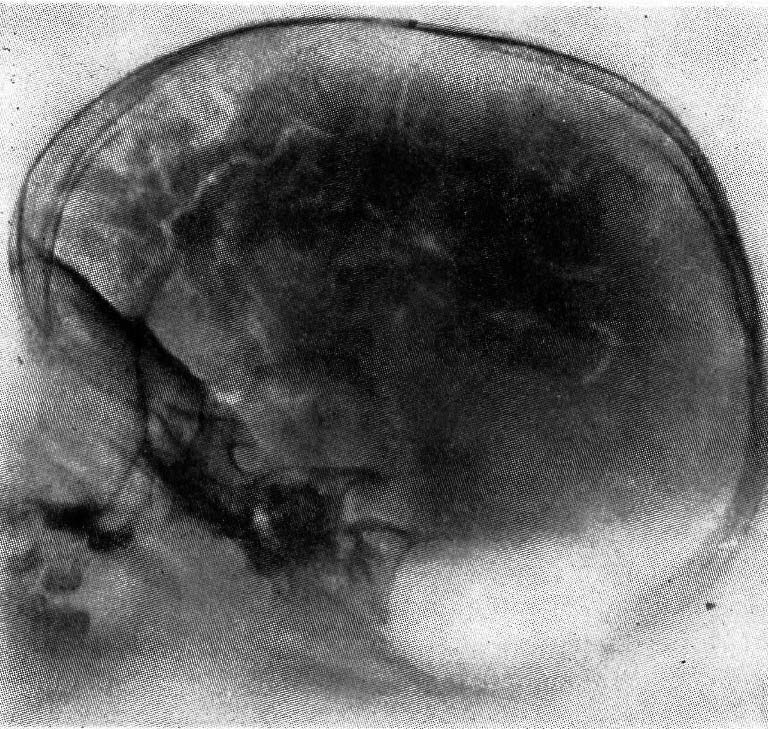

図1. (気)脳室造影.(上図)空気が充盈した側脳室が左右対称の透亮像として認められる[4].(下図)右側頭葉腫瘍.側脳室が左に強く圧排され(→),右大脳半球に占拠性病変があることを示している[5].

1918年,Dandyが発表した(気)脳室造影法(pneumoventriculography, ventriculo-graphy) は[→原著論文],脳室を直接穿刺して40~300mL空気を注入する方法で,大泉門がまだ開いている小児ではここを穿刺できるが,成人では頭蓋穿頭が必要であった.翌1919年には,腰椎穿刺によって空気を注入し,頭蓋内くも膜下腔,脳槽を造影する気脳造影法(encephalography,pneumoencephalography)を発表した[→原著論文](図1).いずれも侵襲の大きな検査であるが,その後CTが登場するまでの約半世紀にわたって脳血管造影とともに,神経放射線診断学の重要な武器となった.